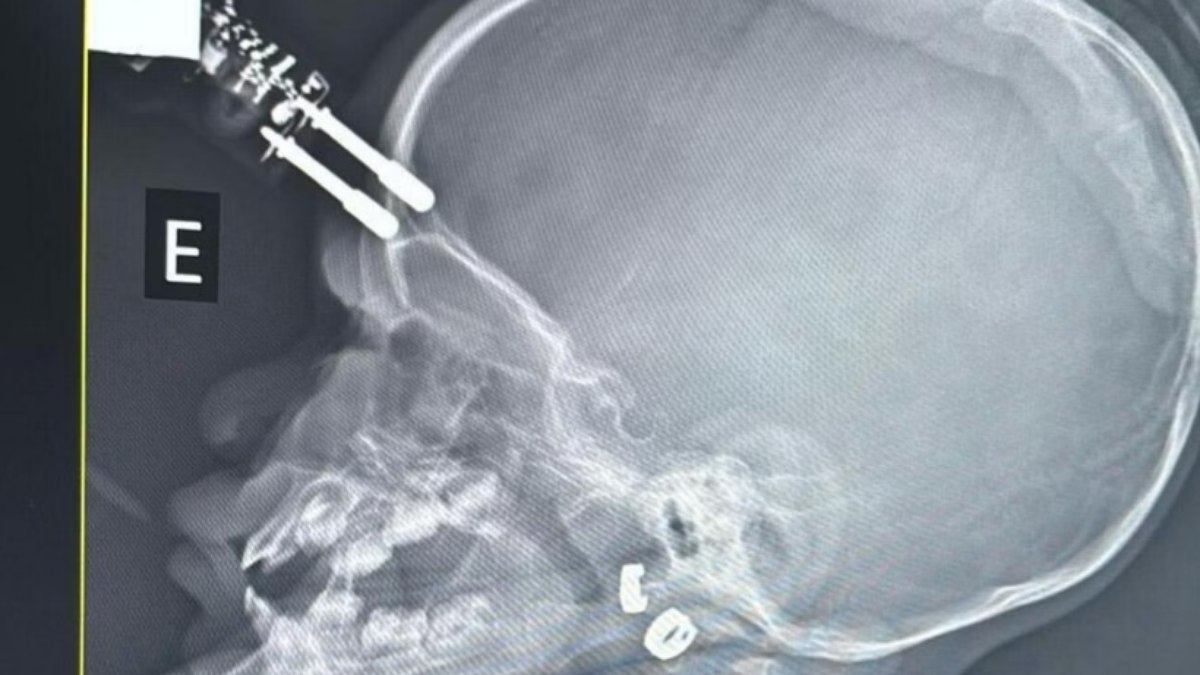

Exames de imagem apontaram que o objeto atravessou o crânio, o que levou a equipe médica a encaminhar a menina imediatamente para o bloco cirúrgico